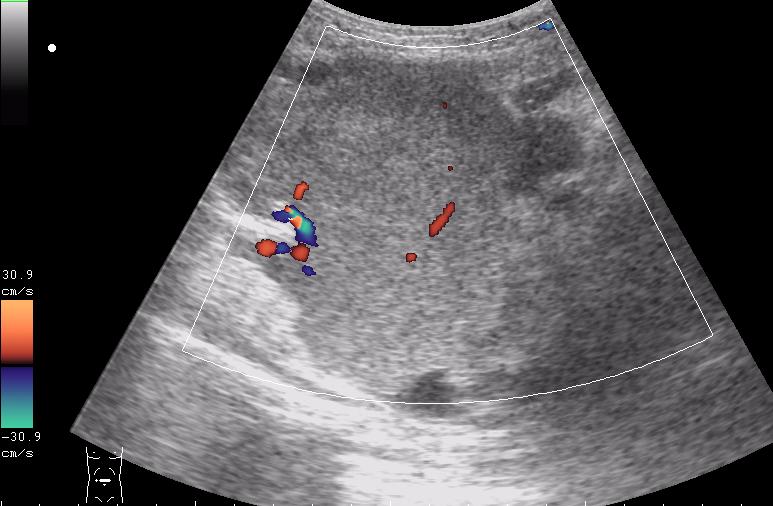

девочка 5 лет, опухоль правого яичника

опухоль правого яичника удалена 3 года назад

Если Это на стороне бывшей операции,то я за рецидив с МТ.Спасибо за бодимаркеры!

получается и в малом тазу и в брюшной полости

выпот похож на геморальгический (???)

первый: малый таз на боку видимо рецидив местный

если то что в брюшной полости не продолжение образования из малого таза....то как вариант mts в брюшине кишечника, в большом сальнике, забр л/у